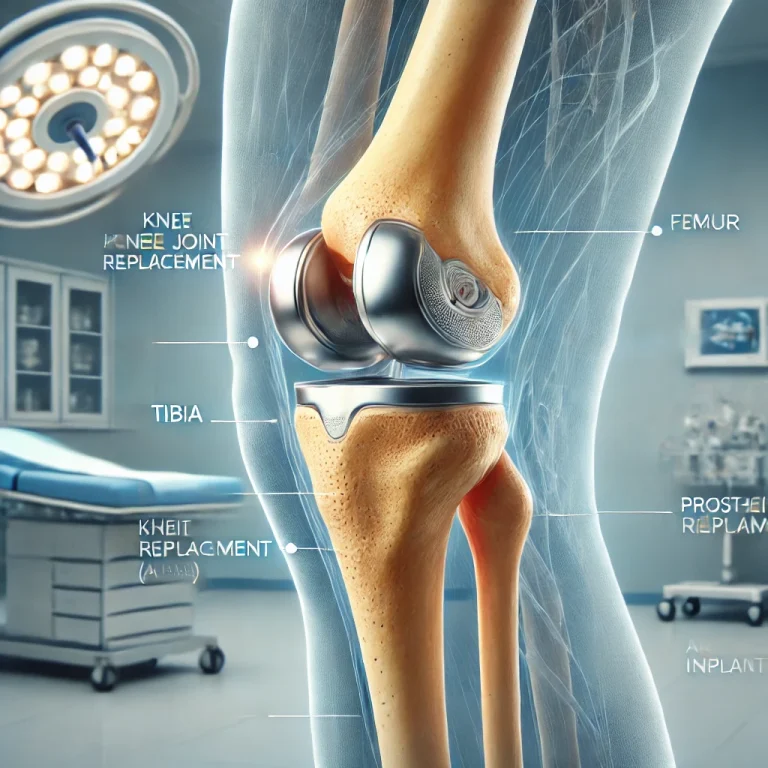

Αρθροπλαστική Γόνατος: Αντικατάσταση της φθαρμένης άρθρωσης του γόνατος με τεχνητά εμφυτεύματα. Ανακουφίζει από τον πόνο και αποκαθιστά την κινητικότητα. Η αποκατάσταση περιλαμβάνει φυσικοθεραπεία και ειδικές ασκήσεις για την ενδυνάμωση του γόνατος.